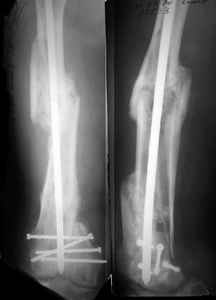

I presented a series of ~25 such cases at EuroTrauma'2004. Many cases were discussed here. I attach am example. Look also recent cases at http://www.hwbf.org/hwb/conf/alex58/scfx.htm,

http://www.hwbf.org/hwb/conf/alex63/alex63.htm

KEMMD> Malpositioning is much too common (recurvatum, varus - valgus).

Did you mark valgus malalignment in that case with LISS you posted Nov 9? Aplication of external distractor can help to avoid the pitfalls but some further development of the technology is necessary to shorten the learning curve.